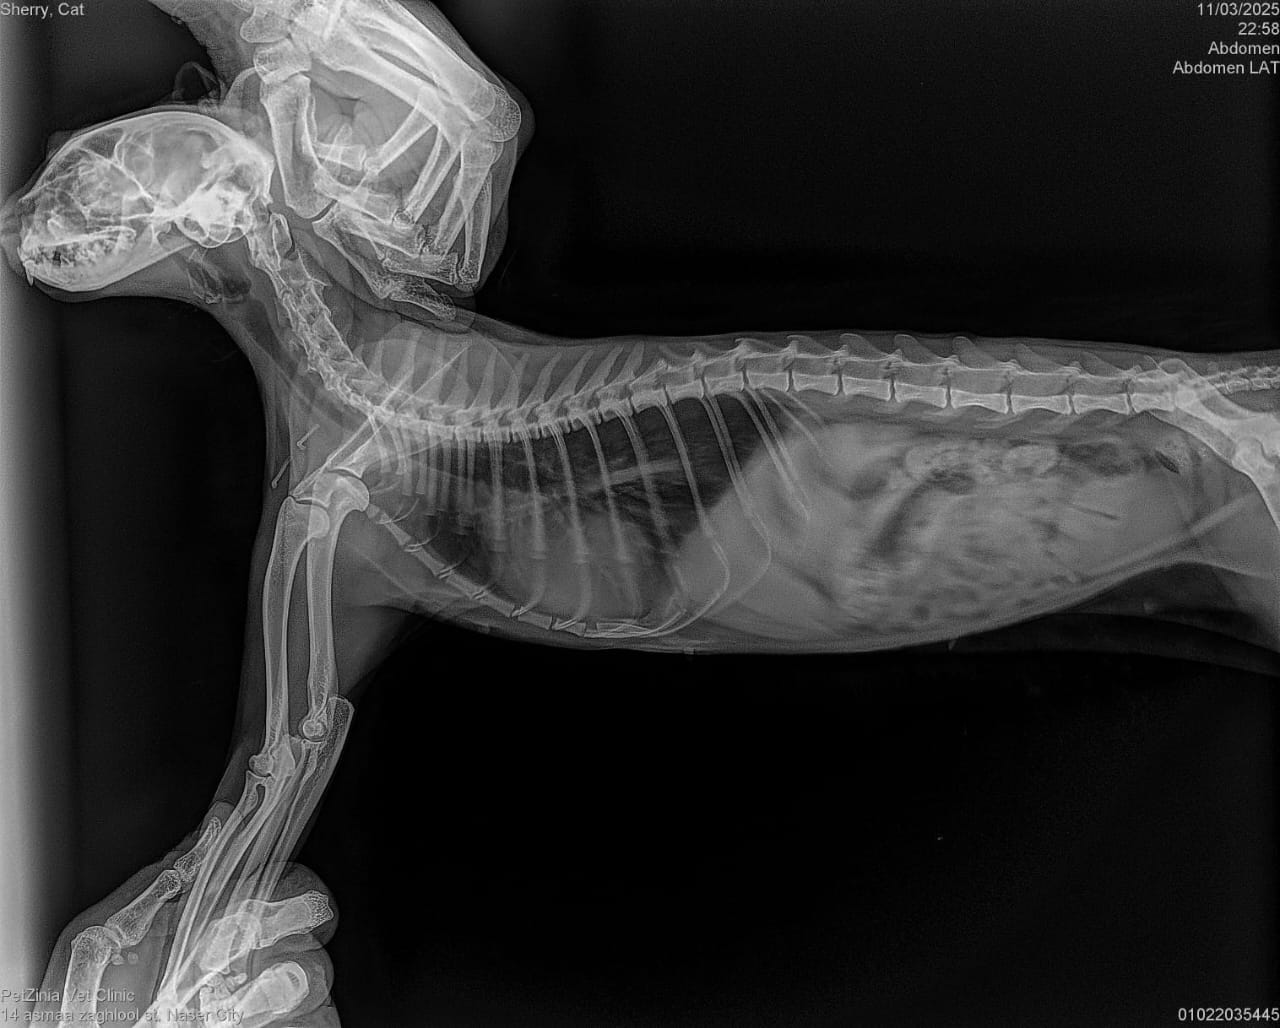

Taxi 6 months, Hit by a car and had a leg Amputation. Stayed more than 8 months at vet and then went to our kahu shelter to get his vaccines and the care need it